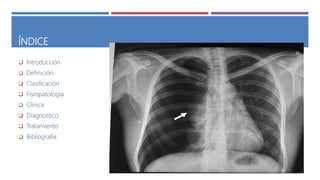

ÍNDICE

 Introducción

 Definición

 Clasificación

 Fisiopatología

 Clínica

 Diagnostico

 Tratamiento

 Bibliografía